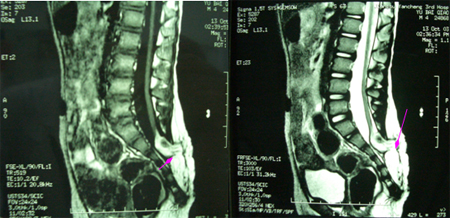

男性,4岁,腰臀后肿物切除术后4年,二便失禁4年。入院查体:臀部上方横形切口瘢痕,约5cm,肛门外口有残留粪便,肛门括约肌松弛,鞍区针刺痛觉减退,耻骨上叩诊浊音。B超:膀胱残余尿量约200ml。术前影像学图片示:先天性腰骶管脊柱裂,脊髓圆锥牵张低位,皮下脂肪疝入椎管内并和脊髓及神经根粘连,脊髓拴系形成。